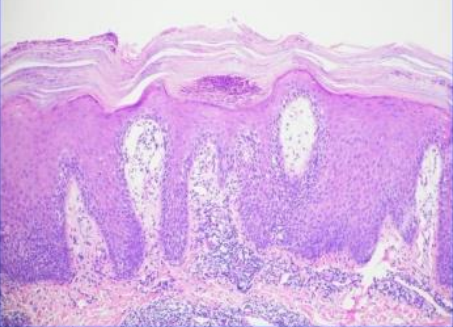

You suspect a patient has malignant melanoma so you have a biopsy done. What do you conclude after seeing this?

Seborrheic Keratosis. Horn cysts, hyperkeratosis and acanthosis with a straight base tells you its not malignant.